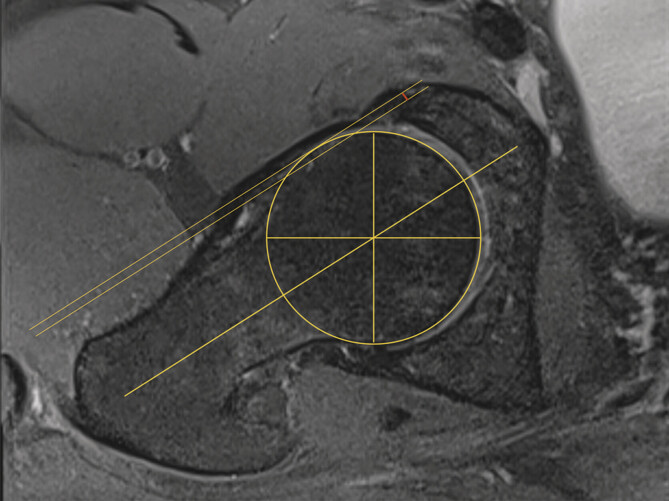

目的:x线,磁共振成像(MRI)和计算机断层扫描(CT)是确定股骨-髋臼撞击(FAI)头颈偏移(HNO)的标准方法。我们的假设是超声辅助确定髋关节CAM畸形的偏移量是一种便宜、无辐射、可靠的替代传统的α角测定方法。方法:在2015年1月至2019年12月期间,根据DEGUM标准程序和MRI进行前纵行髋关节超声检查的髋关节疼痛和疑似CAM撞击患者纳入本单中心研究。偏移量由两名独立调查员通过MRI和超声检查确定三次。结果:285例患者中,110例患者(女性49例,男性61例)符合纳入标准。54例左髋关节和56例右髋关节调查时的平均年龄为54.2岁。进行了1320次测量。MRI (6.11 mm+/-2.37)与超声(5.93 mm+/-2.20)检测HNO无显著差异。平均差值为0.32 mm±0.32 mm (p < 0.05),最大偏差为2.08 mm(异常值)。结论:超声辅助测定头颈偏移是一种可靠、可重复性高的方法,其准确性不低于MRI。超声检查最初可作为定性确定髋关节CAM畸形的替代或附加工具。

Purpose: Native X-ray, magnetic resonance imaging (MRI), and computed tomography (CT) are standard methods for determining head-neck offset (HNO) in femoro-acetabular impingement (FAI). Our hypothesis was that sonography-assisted determination of the offset in CAM deformity of the hip is a cheap, radiation-free, and reliable alternative to conventional alpha-angle determination.

Methods: Patients with hip pain and suspected CAM impingement who underwent anterior-longitudinal hip sonography according to DEGUM standard procedures and MRI were included in this single-center study between January 2015 and December 2019. Offset was determined three times on MRI and sonography by two independent investigators.